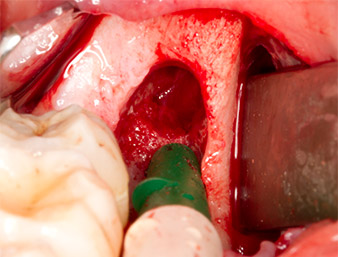

Piezomed S2

Fig. 6: Il residuo di radice viene esposto con attenzione con uno strumento sferico ricoperto in diamante (Piezomed S2) e i bordi dell'osso sono levigati.

residuo di radice 38

Fig. 7: Il residuo di radice 38 (LL8) è ben esposto nel suo alveolo per la successiva rimozione.